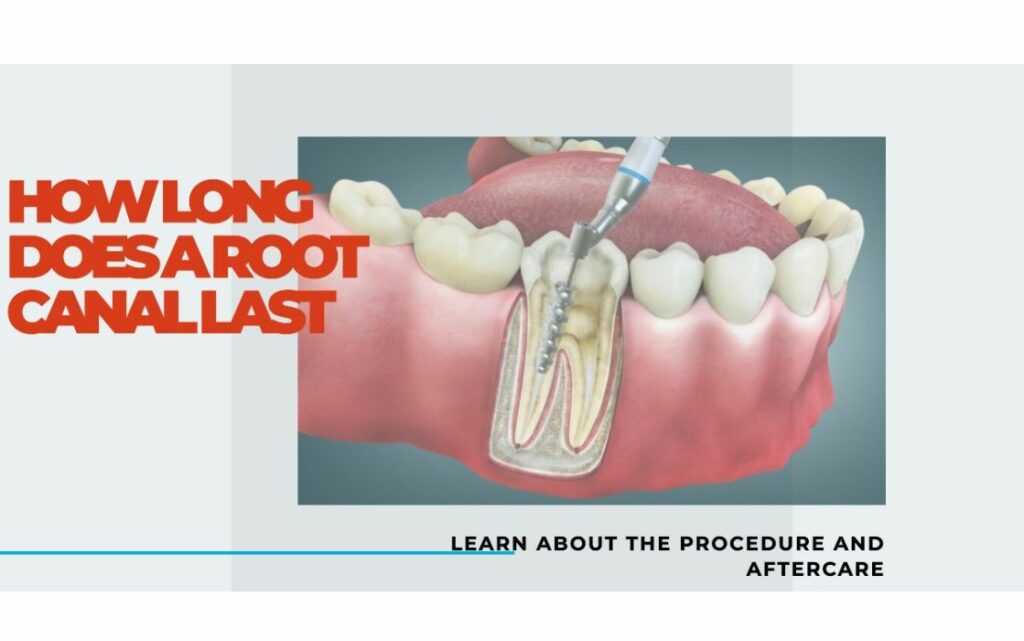

How Long Does a Root Canal Last? Understanding Longevity and Maintenance

A root canal treatment can save a damaged or infected tooth, but many patients wonder how long the results will last. The good news is that with proper care, a root canal-treated tooth can remain functional for decades, sometimes even a lifetime. In this blog, we’ll explore what affects the longevity of a root canal […]